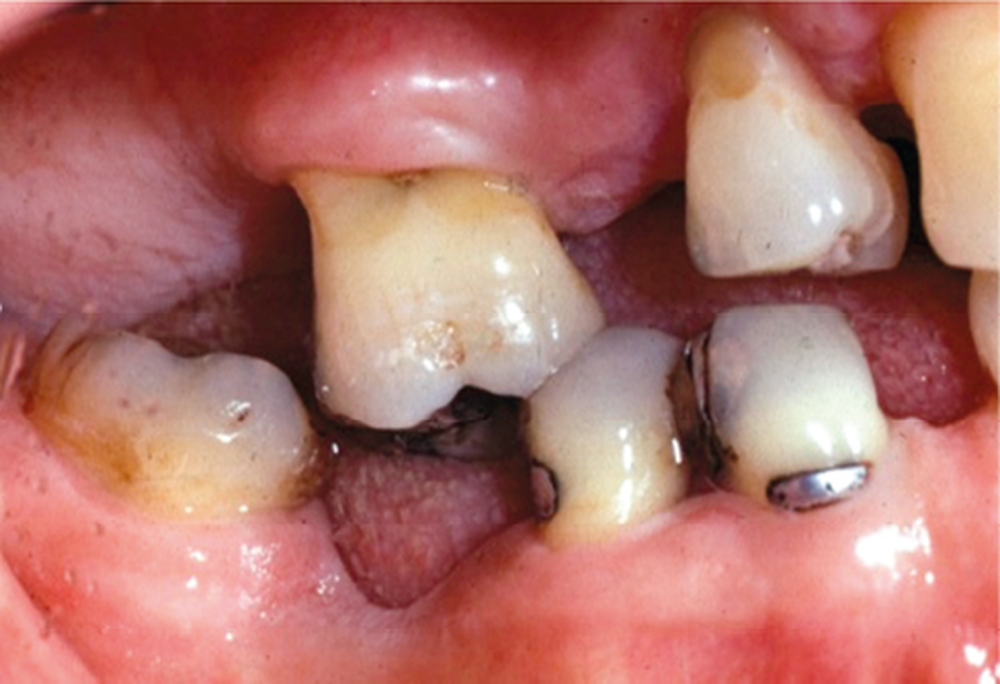

1a-c. Exemple clinique de malocclusion secondaire chez un patient atteint de parodontite avancée. La malocclusion qui se manifeste par la présence de mésio-versions molaires, d’ouverture de diastème et de perte de dimension verticale d’occlusion est ici aggravée par un édentement postérieur non compensé.